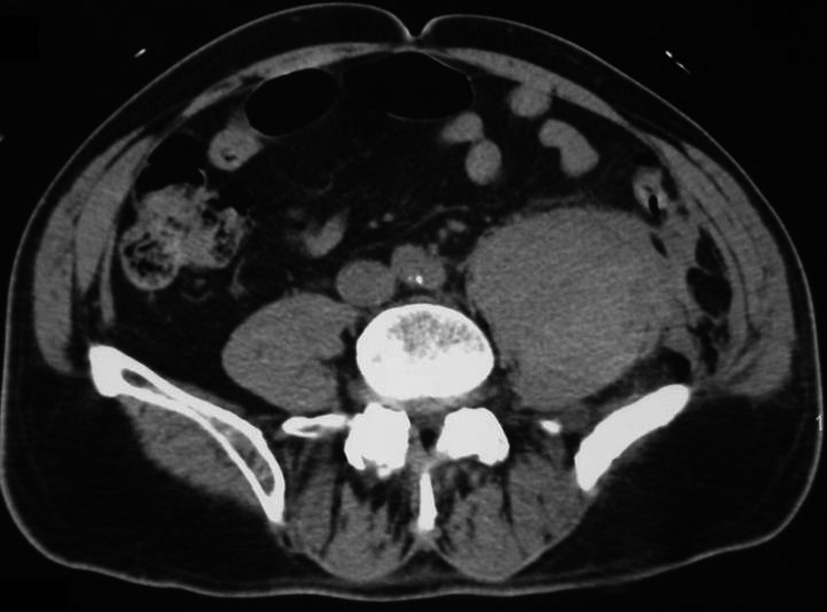

Item 182 : Accidents des anticoagulants

• Iconographie